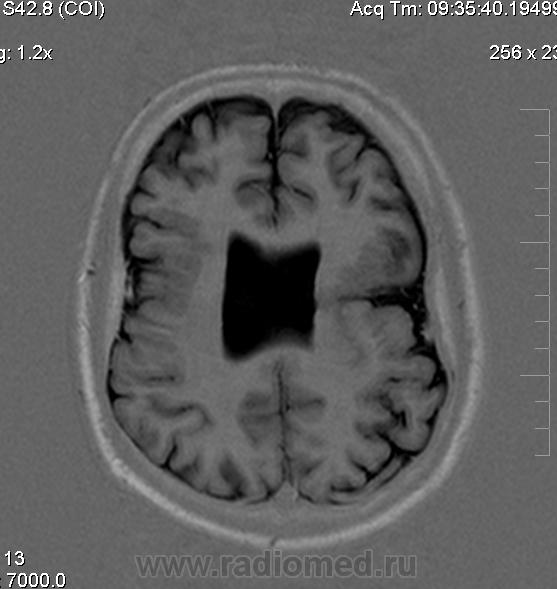

Мужчина 32 лет. Из анамнеза: перинатальное повреждение ЦНС, ДЦП, дизартрия, правосторонний верхний монопарез. С 16 лет приступы эпилепсии.

Аплазия прозрачной перегородки. Шизэнцефалия с открытыми краями в лобно-теменной области слева. Шизэнцефалия с закрытыми краями в лобной области справа? Утолщение коры по контуру расщелин и в области глазничной извилины правой лобной доли. Микрогирия? Гиперостоз костей свода черепа. Уважаемые коллеги, возможно я ошибаюсь, или есть еще аномалия?

На мой взгляд, полимикрогирия двусторонняя (конвекситальные отделы дорзальных отделов лобных долей и частично теменных, а также в базальном отделе полюса правой лобной доли) + закрытая шизенцефалия левой лобно-теменной области. Аплазия прозрачной перегородки (как признаки лобарной голопрозенцефалии).